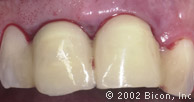

Вид спустя десять недель после установки имплантантов